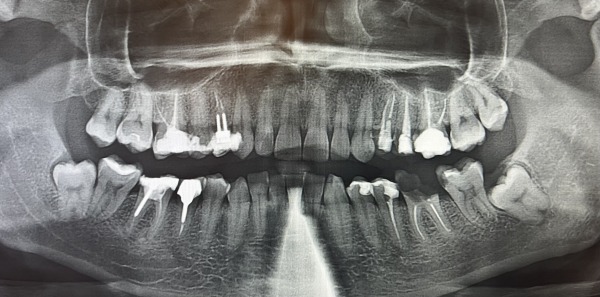

診察をしたところ、左下の奥歯2本が大きな虫歯になっていました。手前は歯の根っこだけになり、奥歯は大きく穴が開いていました。エックス線写真を撮ると、前医での根管治療後に被せ物が装着されないまま中断された状態が確認できました。また、奥歯を中心に何か所か歯と歯の間から虫歯ができていました。

1日目〜3日目 左下の歯の根管治療を行い、治療後のエックス線を撮影しました。